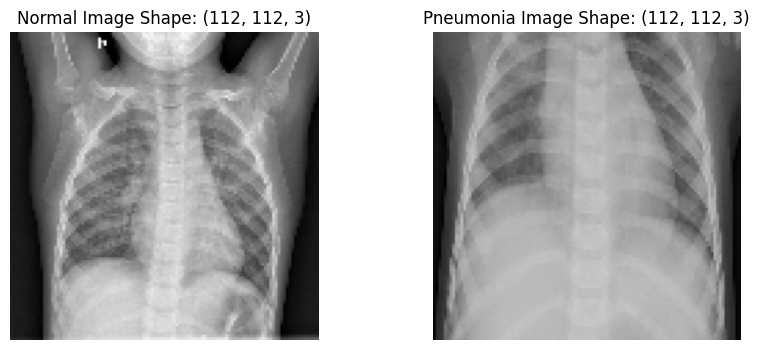

Resize images#

Let’s resize the images to a shape of 112x112 in preparation for CNN input layer

nimage = cv2.resize(nimg, (112,112))

pimage = cv2.resize(pimg, (112,112))

plt.figure(figsize=(10,4))

plt.subplot(1,2,1)

plt.imshow(nimage)

plt.title(f"Normal Image Shape: {nimage.shape}")

plt.axis('off')

plt.subplot(1,2,2)

plt.imshow(pimage)

plt.title(f"Pneumonia Image Shape: {pimage.shape}")

plt.show()

../_images/e9f259c05699b34f5cc9dd0d8c58efe33f6faa913cb5551cf0a73ce3a1a46ab0.png